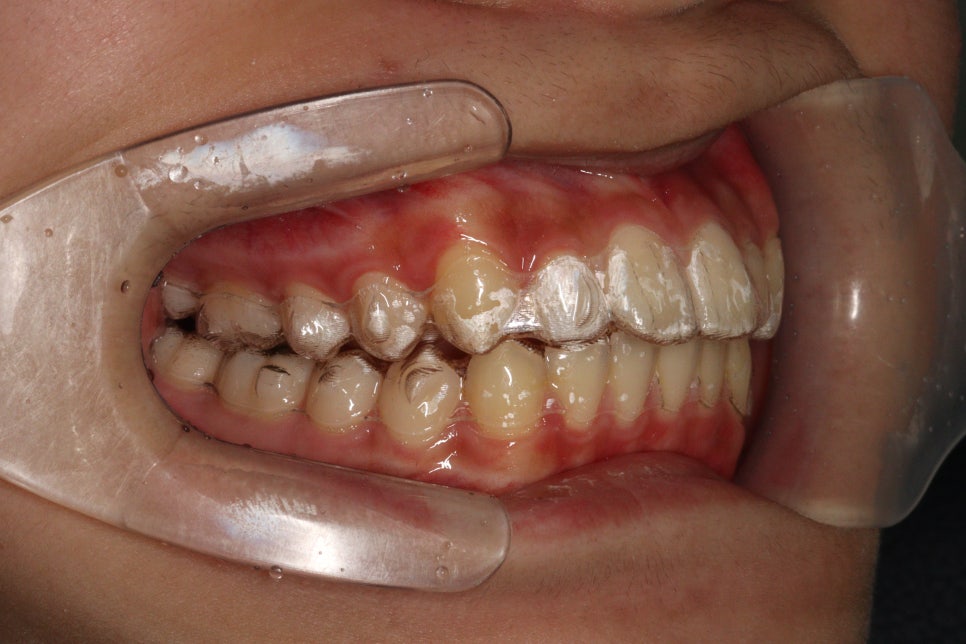

치료 전과 후 입니다.

앞니가 후방이동 한것이 확인됩니다.

우리는 부분교정을 한것이 아니라 간단한 전체교정을 한것입니다.